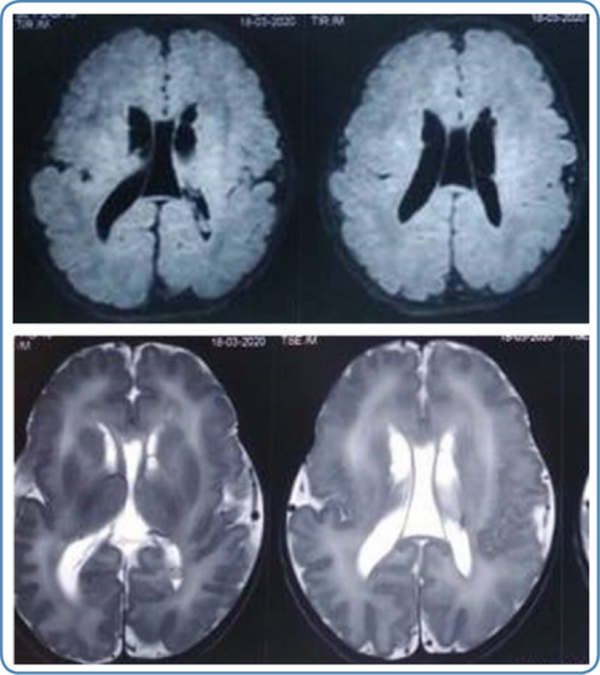

In peroxisomal disorders, specific findings in magnetic resonance imaging (MRI) of the brain are seen only in Zellweger syndrome (Figure 7) and X-ALD. In other peroxisomal disorders, MRI brain findings may provide clues to the diagnosis. MRI brain findings in peroxisomal disorders are listed in Table 4. Typical findings of the MRI brain may not be found in the initial stages of the disease in peroxisomal disorders as they evolve gradually during the disease course. In such a scenario biochemical workup and genetic evaluation would help in the diagnosis.

Figure 7

MRI brain findings in Zellweger syndrome 6A.T2 weighted MRI brain axial view showing germinolytic cysts 6B. T1 weighted MRI brain axial view showing diffuse polymicrogyria